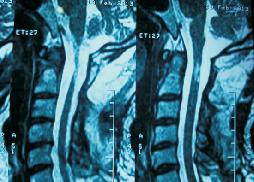

Large CV Junction Intradural Tumor

Large CV Junction Intradural Neurofibroma